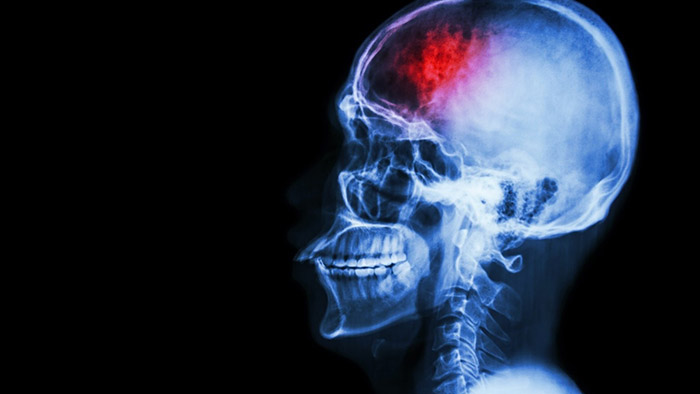

Stroke affects someone on earth every two seconds and has little respect for age (one-third of stroke victims in the US are younger than 65). Stroke’s ischemic aftermath leaves behind a path of devastation, not just to patients but also to their families. Alongside a high mortality rate, those who survive a stroke all too often experience life-changing and debilitating disability. The economic impact of stroke is vast, costing an estimated $34 billion each year in the US alone. Fortunately, significant new clinical data, coupled with notable advances in medical technology, have ushered in an exciting period of change, one that may well revolutionise stroke practice. Time has long been of the essence when it comes to treating stroke – the typical patient loses almost two million neurons each minute in which stroke is untreated, so time is indeed brain. Physicians responding to a patient with suspected stroke will be all too familiar with the ‘golden window’, the period of time in which patients can have a thrombectomy, where the tiny clot capable of such massive destruction is removed through a minimally-invasive image-guided therapy (IGT) procedure. By removing the clot, the flow of blood to the brain is restored, potentially reversing or substantially reducing the long-term effects of stroke.

This golden window has long been deemed to be just six hours. This limited timeframe meant that many patients who could and should have been treated sadly were not. However, research in May 2018 indicated the potential to extend this treatment window by up to four times. The landmark DEFUSE 3 and DAWN trials showed that thrombectomy could be performed effectively in selected patients up to 24 hours after a stroke. While the trial findings are being met with significant excitement from physicians and medical societies, it also means that a larger pool of patients will be eligible for the procedure. Yet few hospitals are equipped with either the appropriate technology or interventional physicians to meet the anticipated demand. It is further indication that we need new ways to ensure that patients are correctly diagnosed, with access to the right expertise, facilities and after-care, within the restricted timeframe. This was further reflected in a recent policy statement published by the American Stroke Association which demands improvements in stroke systems of care to reflect the advances in scientific knowledge and innovations in clinical care. It’s a powerful call to ensure the significant developments that have been made to facilitate optimal stroke care delivery and improve patient outcomes. Notably, one of the recommendations in the policy statement called for emergency workers to carefully consider which hospital can give stroke patients the best care, within a fifteen-minute journey, highlighting the importance of optimum treatment in this time-sensitive situation. There’s no doubt that there is great progress being made. The ‘stroke ambulance’ – an ambulance equipped with computed tomography (CT) imaging technology to clarify whether the patient has had a stroke or not and whether they are a candidate for thrombectomy. If deemed a suitable candidate, the patient can be swiftly diverted to the nearest stroke centre capable of performing a thrombectomy. Already in use in several cities, including New York and Berlin, the stroke ambulance clearly saves time, but it is neither cost-efficient or practical to equip all ambulances with such capabilities.